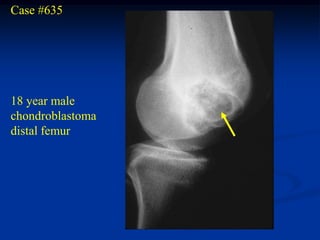

Case #635

18 year male

chondroblastoma

distal femur

CT scan

Photomic